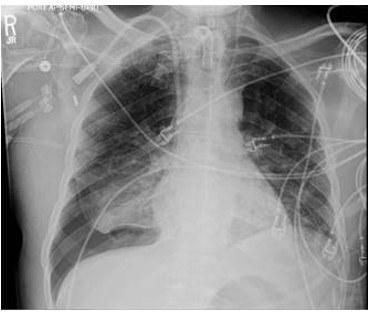

A 79-year-old male with a past medical history of Alzheimer’s dementia, chronic respiratory failure with tracheostomy and ventilator dependence, end stage renal disease, and atrial fibrillation is admitted to the intensive care unit from an outside hospital with septic shock. Urine cultures were positive for Vancomycin-resistant Enterococcus faecium and the tracheal aspirate was positive for Stenotrophomonas, Pseudomonas, and Proteus species. Chest x-ray demonstrated a right pleural effusion, which was present since outside hospital admission two and a half weeks prior. Decision was made to drainto rule out a source of persistent septic shock. Ultrasound guided thoracentesis was performed with ultrasound visualization during therapeutic aspiration. A total of 1400 cc of serous fluid was removed. After the procedure, the patient was briefly hypotensive, which resolved without intervention. Oxygenation remained stable. Pleural studies revealed a paucicellular lymphocytic transudate.

What is the finding?

A. Tension pneumothorax

B. Pneumothorax ex vacuo

C. Re-expansion pulmonary edema

D. Hemothorax